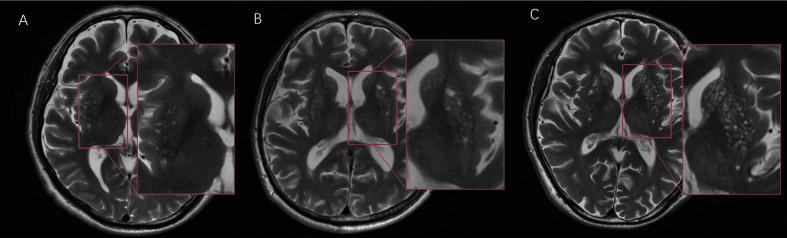

In the clinic, practitioners encounter many patients with an abnormal pattern of dense punctate magnetic resonance imaging (MRI) signal in the basal ganglia, a phenomenon known as "cheese sign". This sign is reported as common in cerebrovascular diseases, dementia, and old age. Recently, cheese sign has been speculated to consist of dense perivascular space (PVS). This study aimed to assess the lesion types of cheese sign and analyze the correlation between this sign and vascular disease risk factors.

A total of 812 patients from Peking Union Medical College Hospital (PUMCH) dementia cohort were enrolled. We analyzed the relationship between cheese sign and vascular risk. For assessing cheese sign and defining its degree, the abnormal punctate signals were classified into basal ganglia hyperintensity (BGH), PVS, lacunae/infarctions and microbleeds, and counted separately. Each type of lesion was rated on a four-level scale, and then the sum was calculated; this total was defined as the cheese sign score. Fazekas and Age-Related White Matter Changes (ARWMC) scores were used to evaluate the paraventricular, deep, and subcortical gray/white matter hyperintensities.

RESULTS

A total of 118 patients (14.5%) in this dementia cohort were found to have cheese sign. Age (odds ratio [OR]: 1.090, 95% confidence interval [CI]: 1.064-1.120, P <0.001), hypertension (OR: 1.828, 95% CI: 1.123-2.983, P = 0.014), and stroke (OR: 1.901, 95% CI: 1.092-3.259, P = 0.025) were risk factors for cheese sign. There was no significant relationship between diabetes, hyperlipidemia, and cheese sign. The main components of cheese sign were BGH, PVS, and lacunae/infarction. The proportion of PVS increased with cheese sign severity.

CONCLUSIONS

The risk factors for cheese sign were hypertension, age, and stroke. Cheese sign consists of BGH, PVS, and lacunae/infarction.